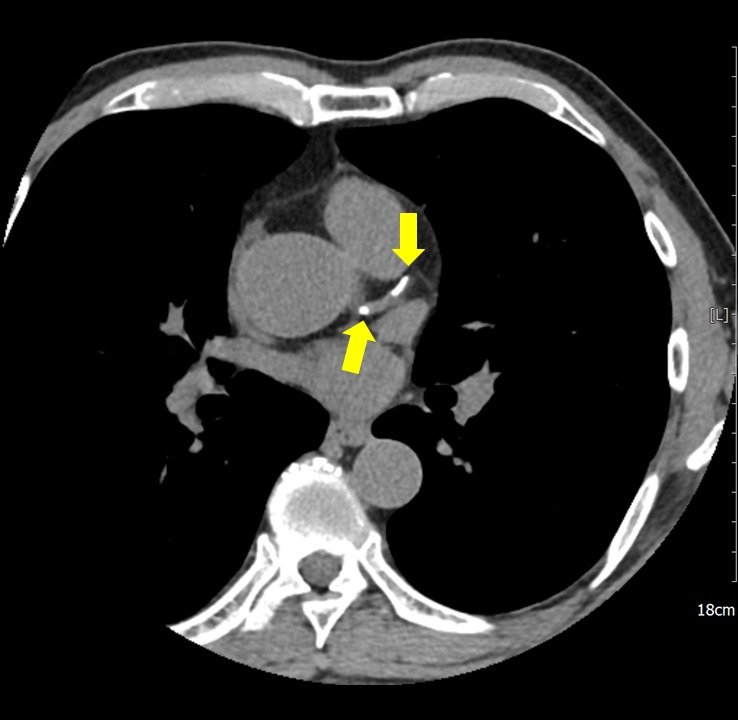

관상동맥석회화/강북삼성병원 제공

(서울=뉴스1) 강승지 기자 = 45세 미만 젊은층에서 관상동맥 석회화로 인한 심혈관 질환 사망도가 중·장년층보다 매우 높다는 연구 결과가 나왔다. 관상동맥 석회화란 심장의 관상동맥에 칼슘이 쌓여 혈관이 딱딱하게 굳어진 현상을 말한다.

교수팀은 2010~2020년 병원 건강검진센터에서 관상동맥 컴퓨터단층촬영(CT)을 한 성인 16만821명을 대상으로 관상동맥 석회화 점수와 심혈관 질환의 사망 위험도를 분석했다.